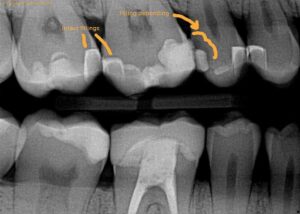

How Dentists Diagnose the Problem

Your dentist may use:

- X-rays

- Bite tests

- Visual examination

- Sensitivity testing

The goal is to identify the exact source rather than simply treating symptoms.